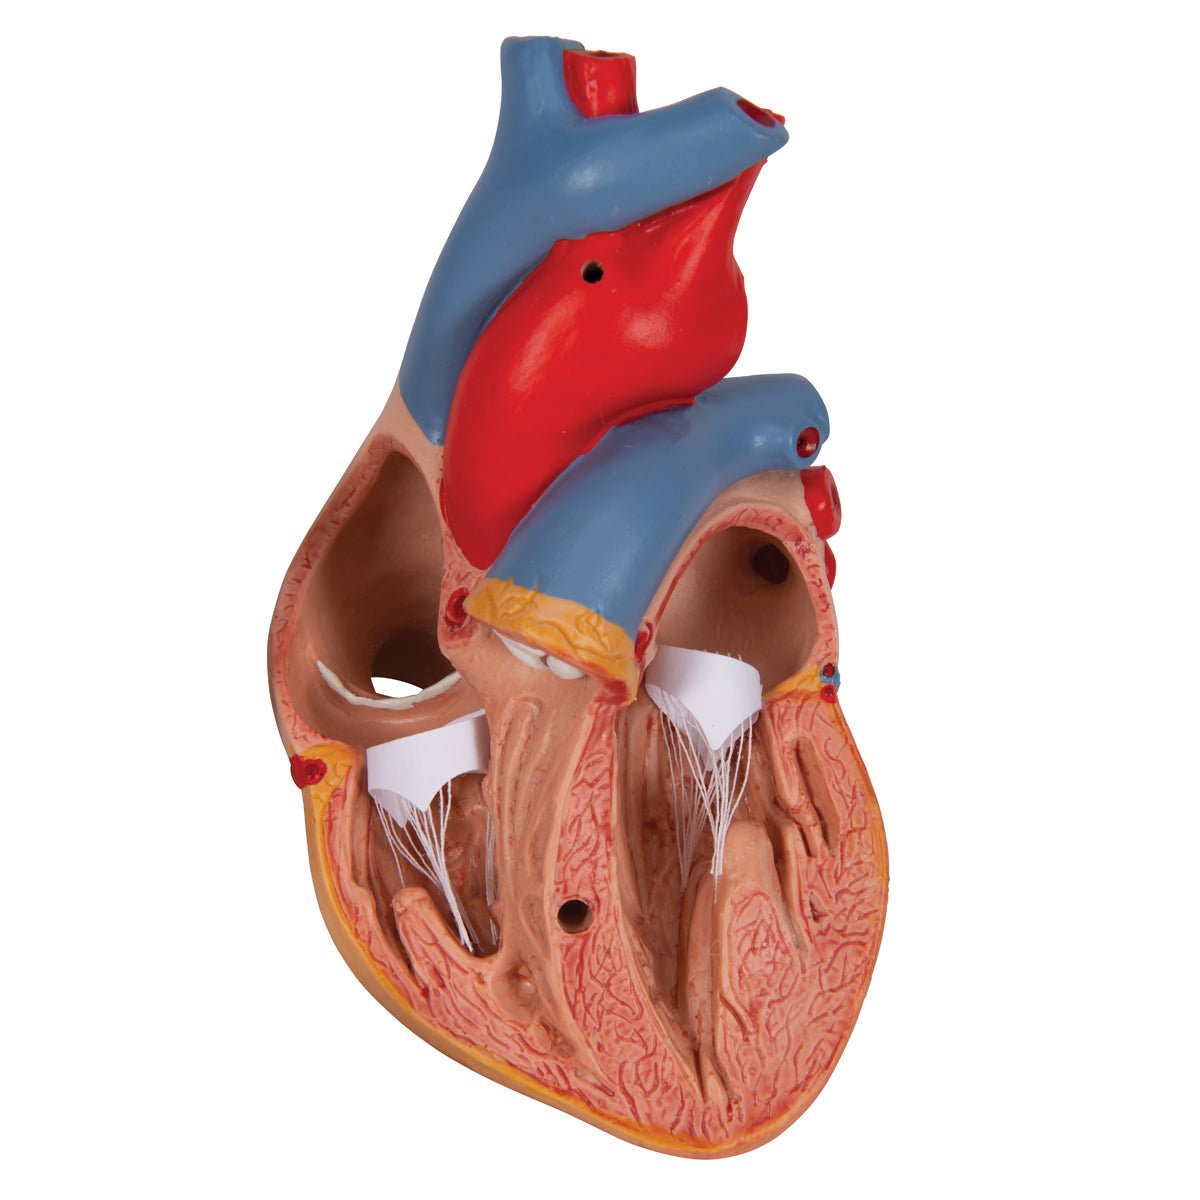

Anatomical models

Selling anatomical models is the mainstay of eAnatomi, although we also spend a lot of resources developing our own anatomical materials such as posters. Anatomical models are used for various purposes and can show both defined tissues, organs and organ systems. Are you looking for a simple model of bone tissue or perhaps an advanced torso model based on MRI technology, you can find it all at eanatomi.com.